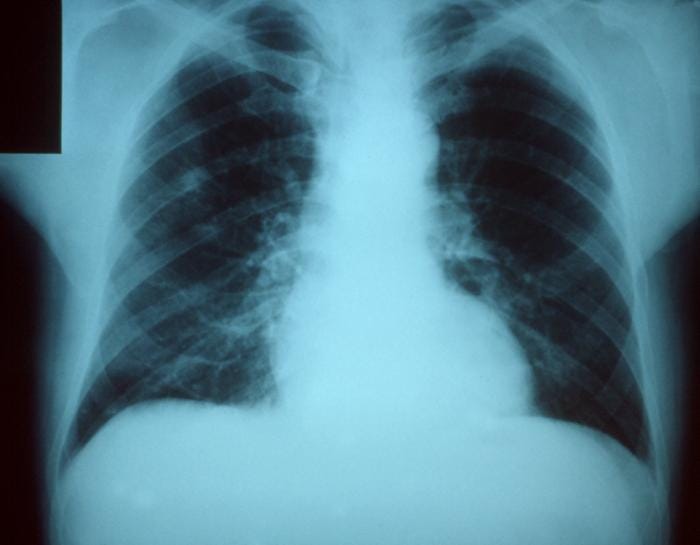

(image: Wikipedia)